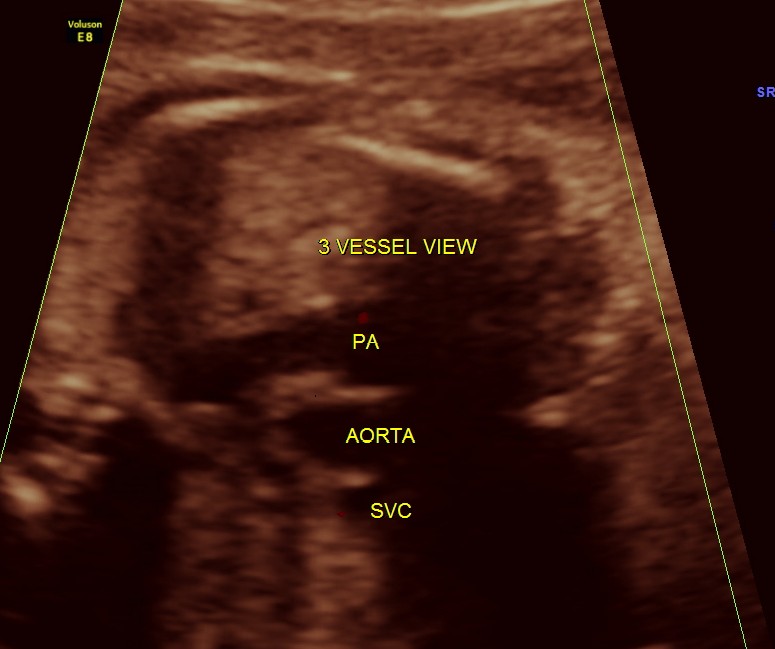

The next 2 images show the findings of the fetal heart. Significant hypertrophy of the septal and apical regions of the Left ventricle are seen.